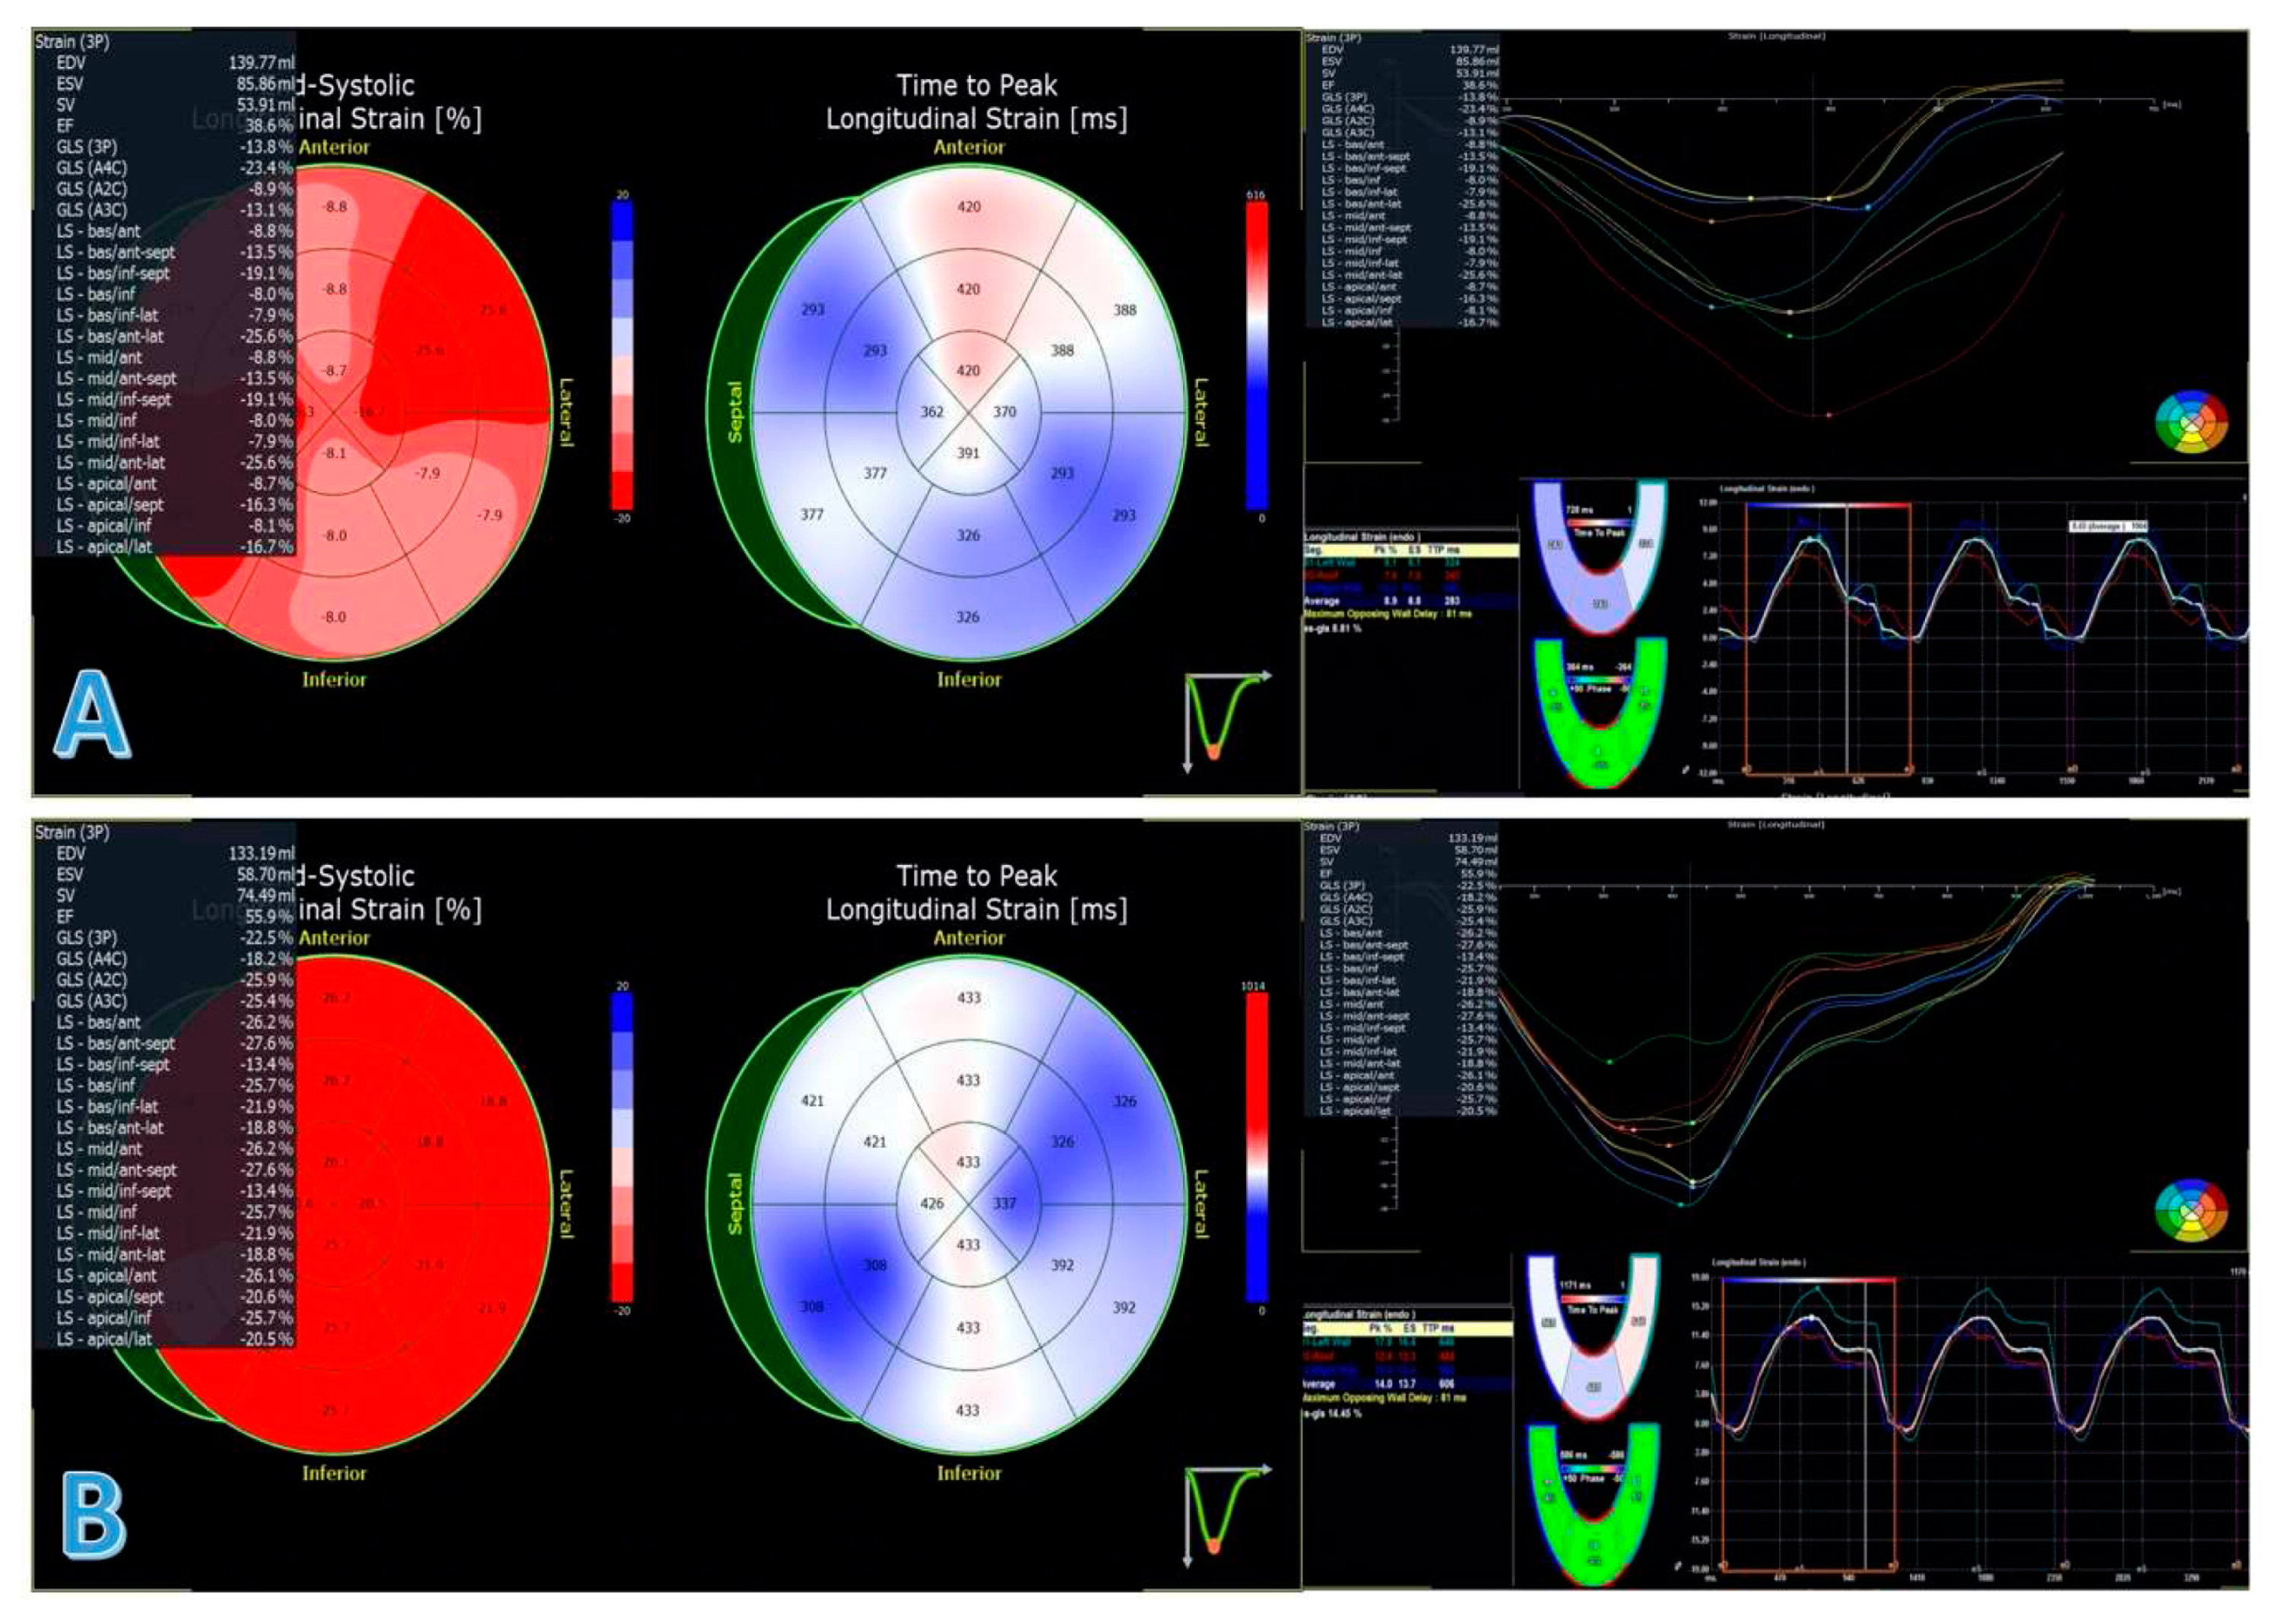

| LVGLS (%) | −8.3 ± 4 | −12 ± 4.7 | <0.001 |